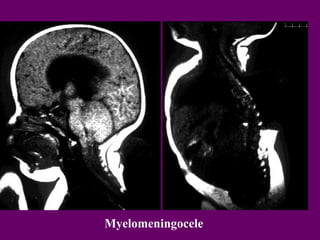

Baát

thöôø

ng

Myelomeningocele

Myelomeningocele +Lipoma